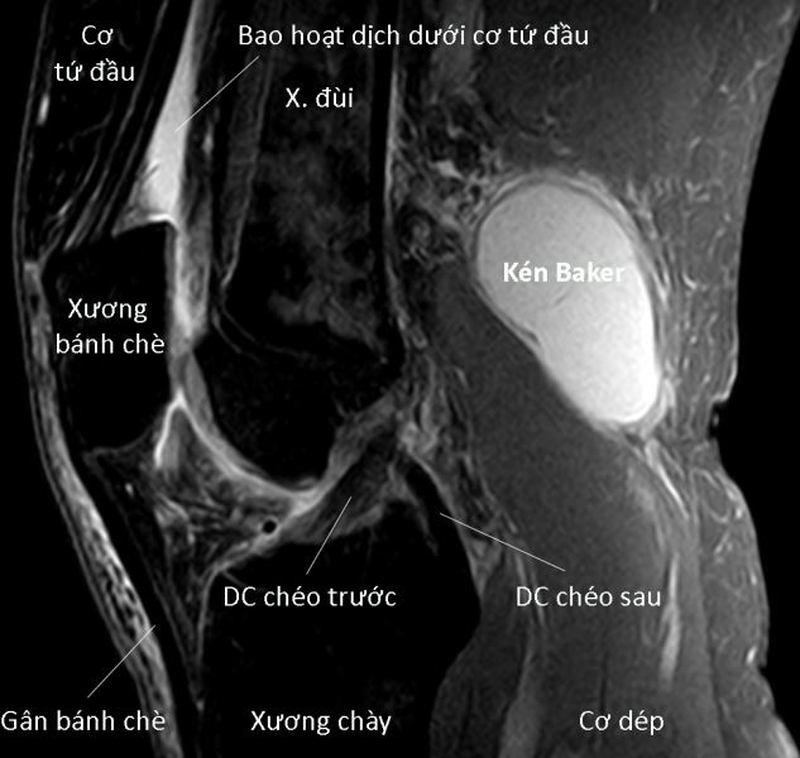

Siêu âm khớp gối giúp phát hiện các tổn thương nào? 2 Hình ảnh mặt cắt khớp gối

• Bệnh lý kén Baker ở vùng khoeo chân.